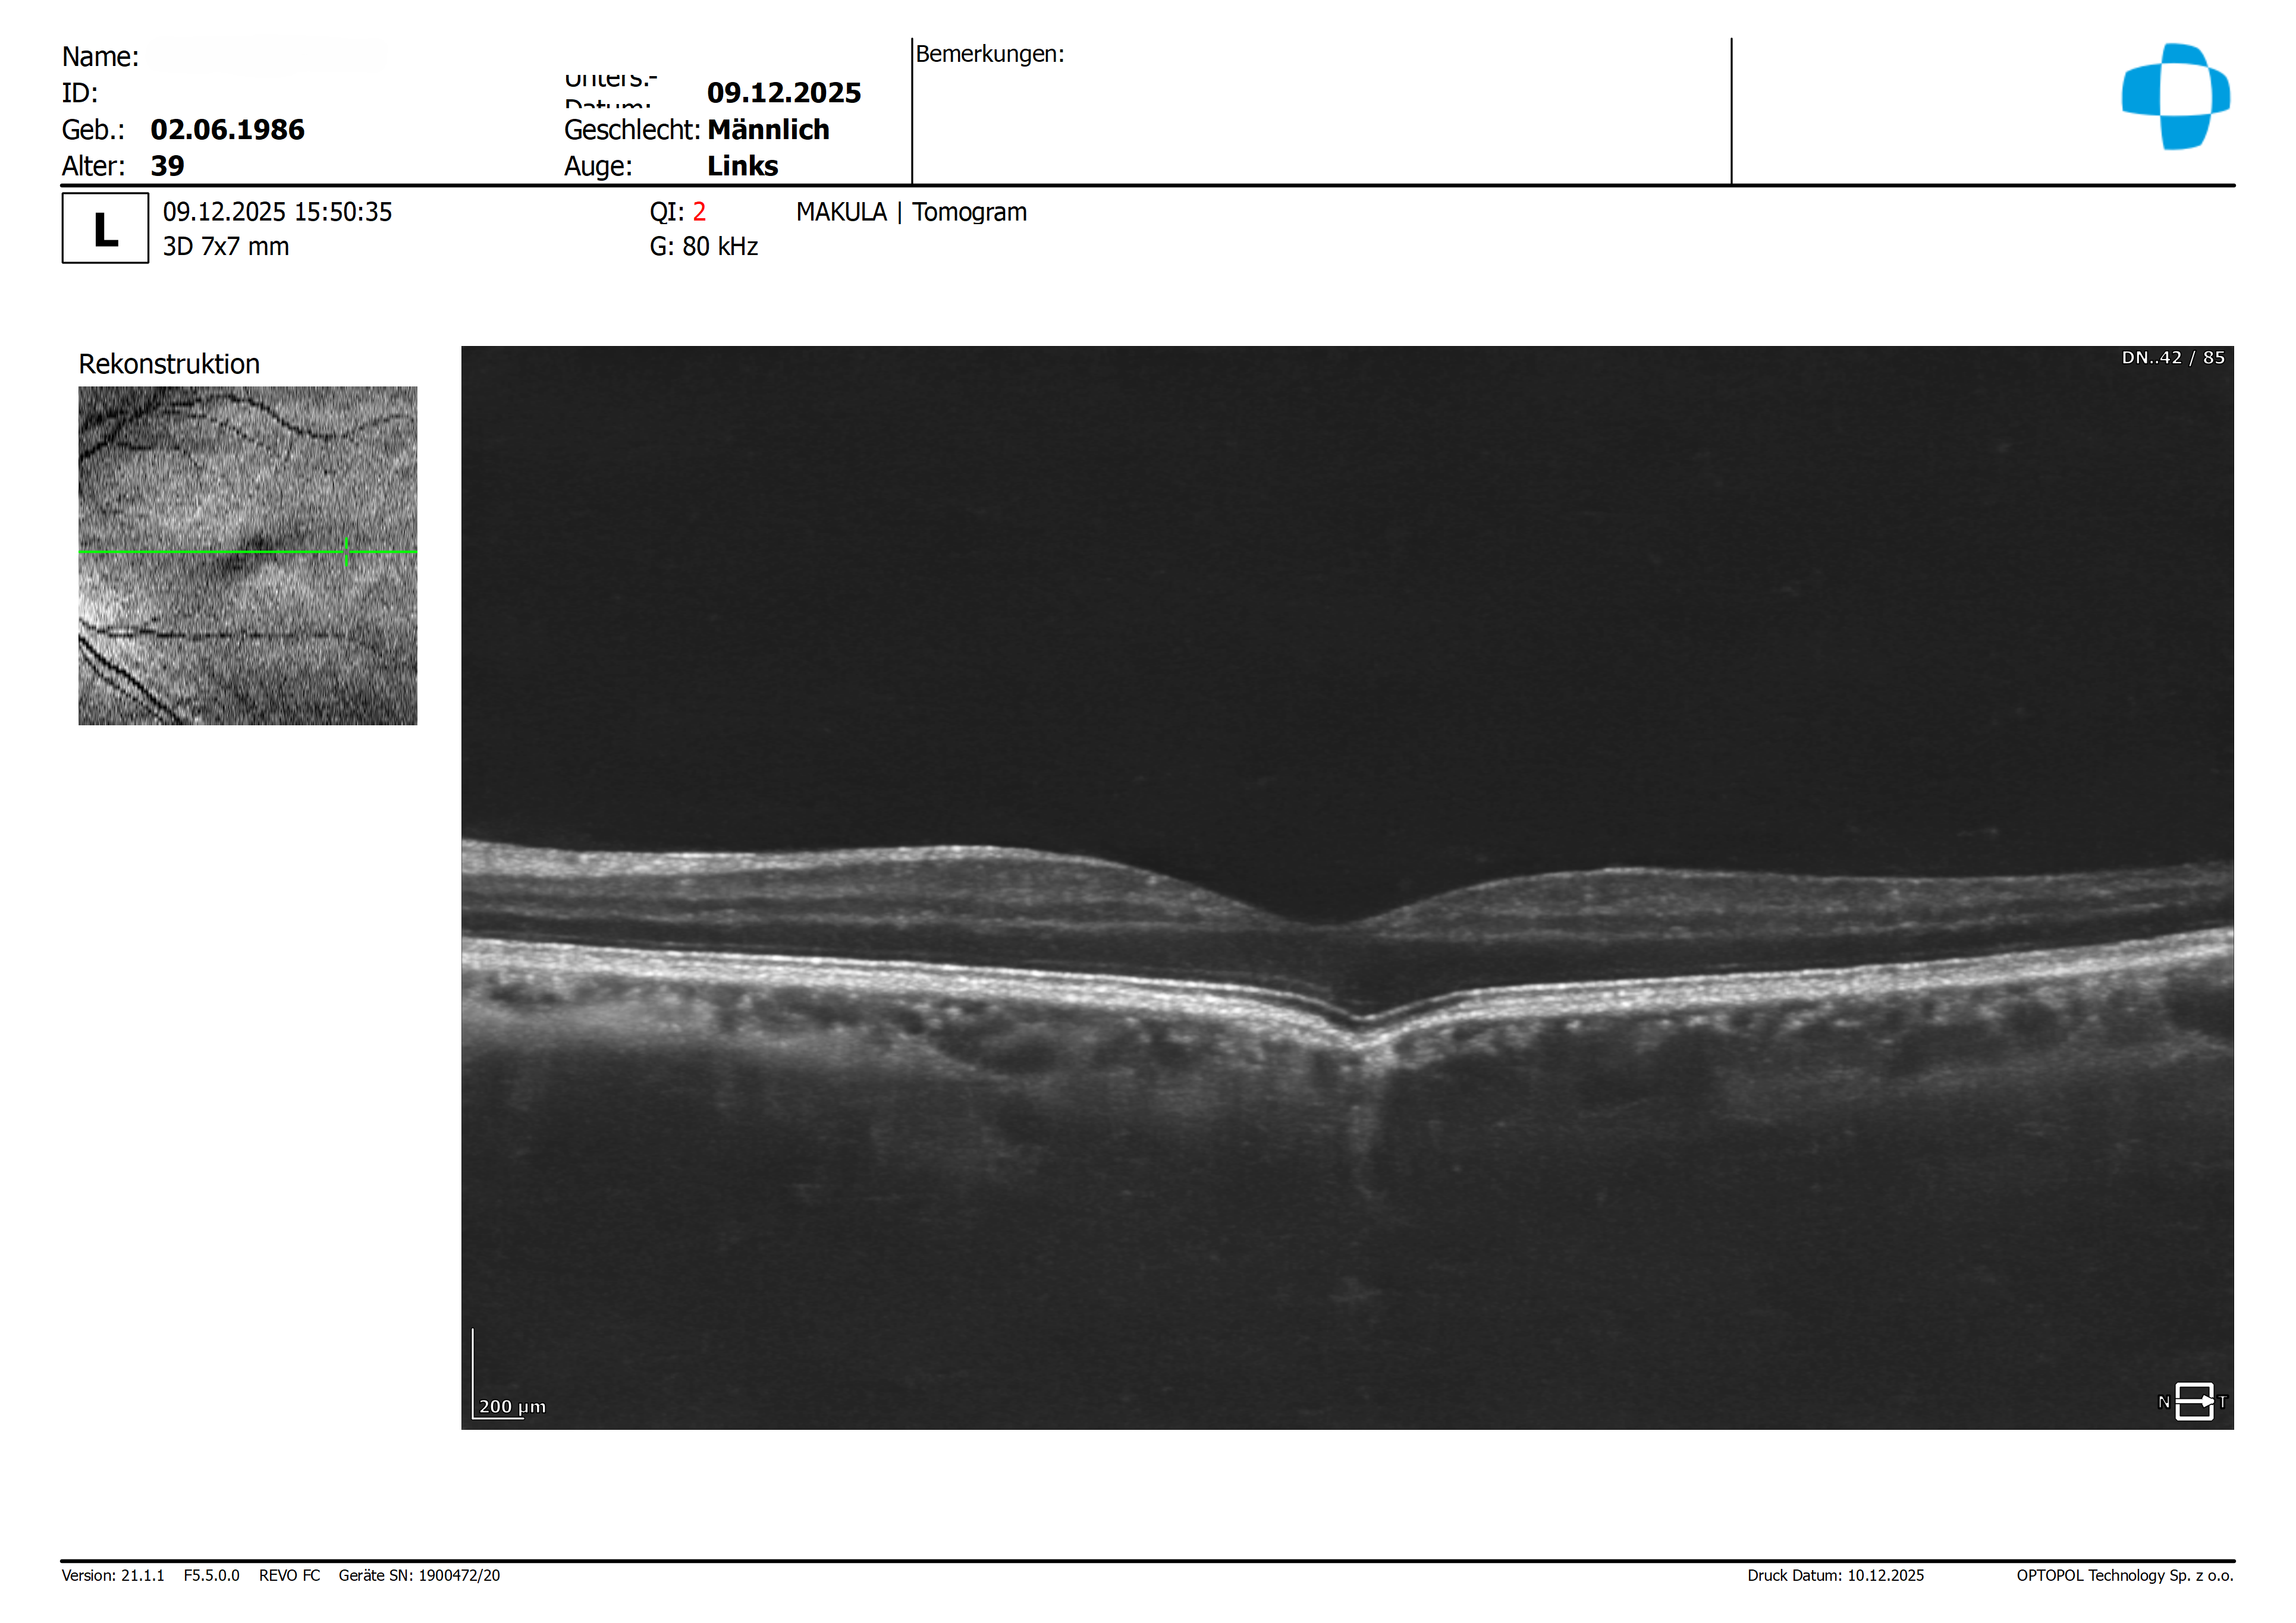

Wie aus den Bildern ersichtlich, ist die linke Foveola abweichend zu der Norm.

Im Bereich des Pigmentepithels ist die Schicht konkav und zur äußeren Schicht der Retina nach links verschoben.

Auf den vorliegenden Bildern zeigt sich eine atypische Veränderung der Bulbusform im zentralen Foveabereich. Der Bulbus erscheint dort leicht eingezogen, was die beschriebene konkave Konfiguration der äußeren Netzhaut- und Aderhautstrukturen gut erklärt.

Meiner Interpretation nach handelt es sich hierbei weniger um eine pathologische Veränderung als vielmehr um eine anatomische Anomalie, die am ehesten im Sinne eines Mini-Staphyloms zu deuten ist. Beruhigend ist in diesem Zusammenhang, dass sowohl der Netzhautbefund als auch der Visus unauffällig sind.

Differentialdiagnostisch – wie von Enno bereits erwähnt – könnten erworbene Schäden wie eine Maculopathia solaris oder ein Laserschaden in Betracht gezogen werden. In diesen Fällen wäre jedoch typischerweise mit einem deutlichen funktionellen Defizit zu rechnen, das vom Patienten auch als positives Skotom wahrgenommen würde. Zudem zeigt sich bei beiden Entitäten charakteristischerweise ein scharf begrenzter, „wie ausgestanzt“ wirkender Defekt des RPE, was hier eindeutig nicht der Fall ist.

Insgesamt gehe ich daher von einer Normvariante ohne pathologischen Zusammenhang aus. Dennoch empfehle ich zur Sicherheit eine Verlaufskontrolle in etwa 6 Monaten inklusive Visuserhebung und OCT.